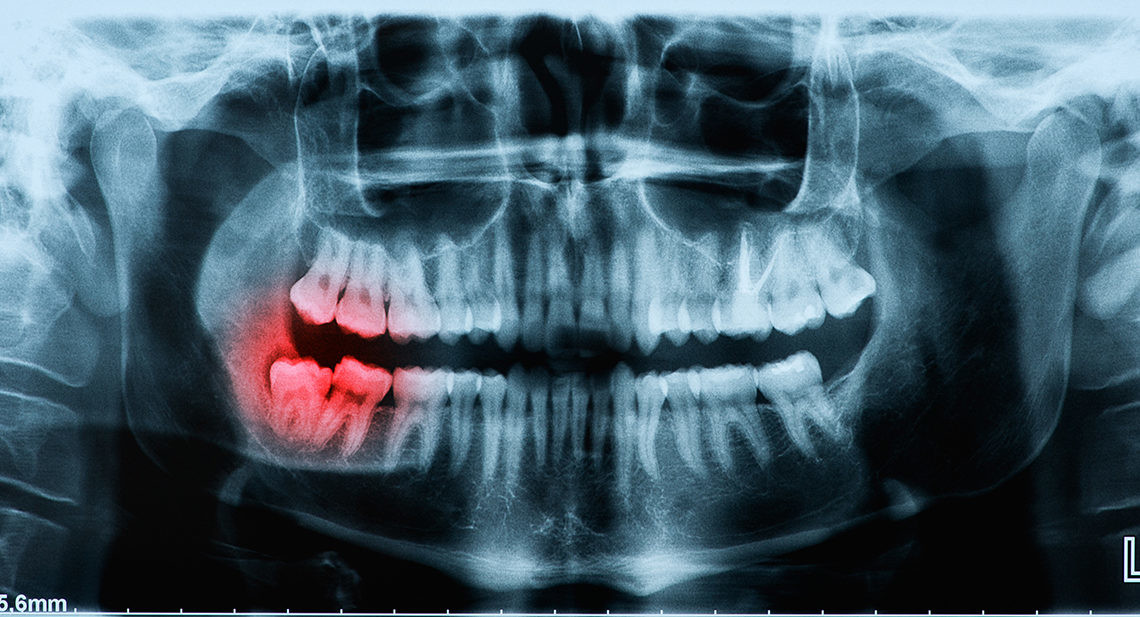

As wisdom teeth are the last to come through, there may be limited space in your mouth. As they try to erupt through your gum, another tooth may already be occupying the same spot. Your wisdom tooth may come through at an unnatural angle, or even crack as it forces its way out.

Wisdom teeth may be more likely to break than your other teeth if they have not erupted correctly. You may find it more challenging to use those teeth to chew, and there is a greater chance of decay if it is harder to clean thoroughly around that area.

As with any other tooth, your wisdom teeth are susceptible to blunt force trauma, such as an impact on your jaw, or biting into something hard. If your teeth crack, or fragments of your wisdom tooth break off, this is likely to cause discomfort.

Risks from Having a Broken Wisdom Tooth

Bacteria can thrive in gaps where bits of the tooth broke. A gap in a wisdom tooth is a hospitable environment for an infection and a weak point in the tooth.

Additionally, a broken or cracked wisdom tooth puts the entire tooth’s health at risk. Bacteria can invade the tooth and infect the dental pulp. In those cases, the tooth must either be extracted or given a root canal treatment. In most cases, it’s better just to remove the tooth.